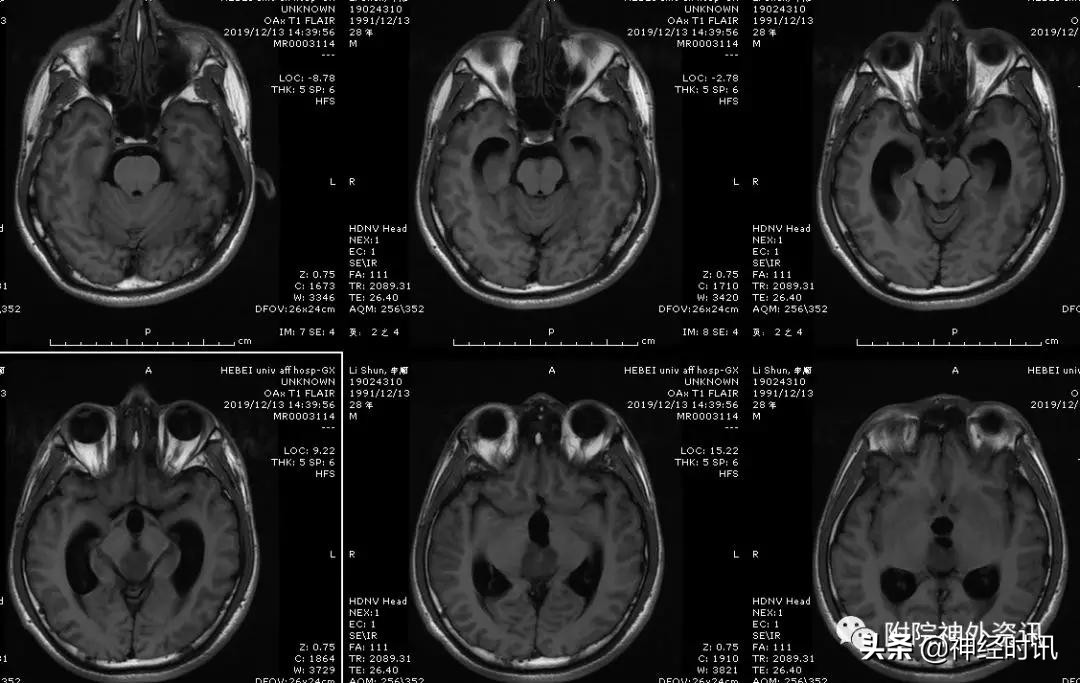

附近期手术一例

男性,28岁,主因复视20余天入院,查体双瞳孔不等大,直径左=3. 5mm,右=3.0 mm,对光反射迟钝,双眼上视困难,左眼眼位异常,向内下斜视。